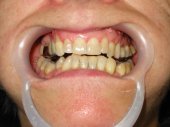

Alteraciones de los tejidos parodontales (encía, ligamento y hueso) por problemas funcionales |

Sangrado gingival espontáneo, infecciones

en las encías o movilidad dentaria debidos al desequilibrio oclusal